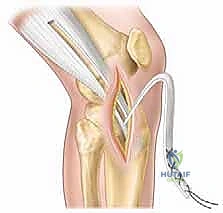

شكل 3: تجهيز الطعم الوتري (Graft Preparation) بعناية فائقة. يتم اختيار الطعم المناسب وتجهيزه ليكون بالقوة والسمك المناسبين لركبة الطفل.

يتم تقسيم التقنيات الجراحية إلى ثلاث فئات رئيسية:

1. التقنيات خارج المفصل (Extra-articular) والمحافظة تماماً على المشاشة (Physeal-Sparing)

تُستخدم هذه التقنية للأطفال الصغار جداً (مرحلة ما قبل البلوغ، عادة تحت سن 10-11 سنة)، حيث تكون صفائح النمو مفتوحة على مصراعيها والنمو المتبقي كبير جداً.

* كيف تتم؟ يتم استخدام وتر (مثل الشريط الحرقفي الظنبوبي IT Band) وتمريره حول العظام وخارج المفصل أو من خلال المشاشة (Epiphysis) فقط، دون حفر أي أنفاق تقطع صفيحة النمو (Physis) لا في عظم الفخذ ولا في عظم الساق.

* الميزة: أمان بنسبة 100% تقريباً لصفائح النمو.